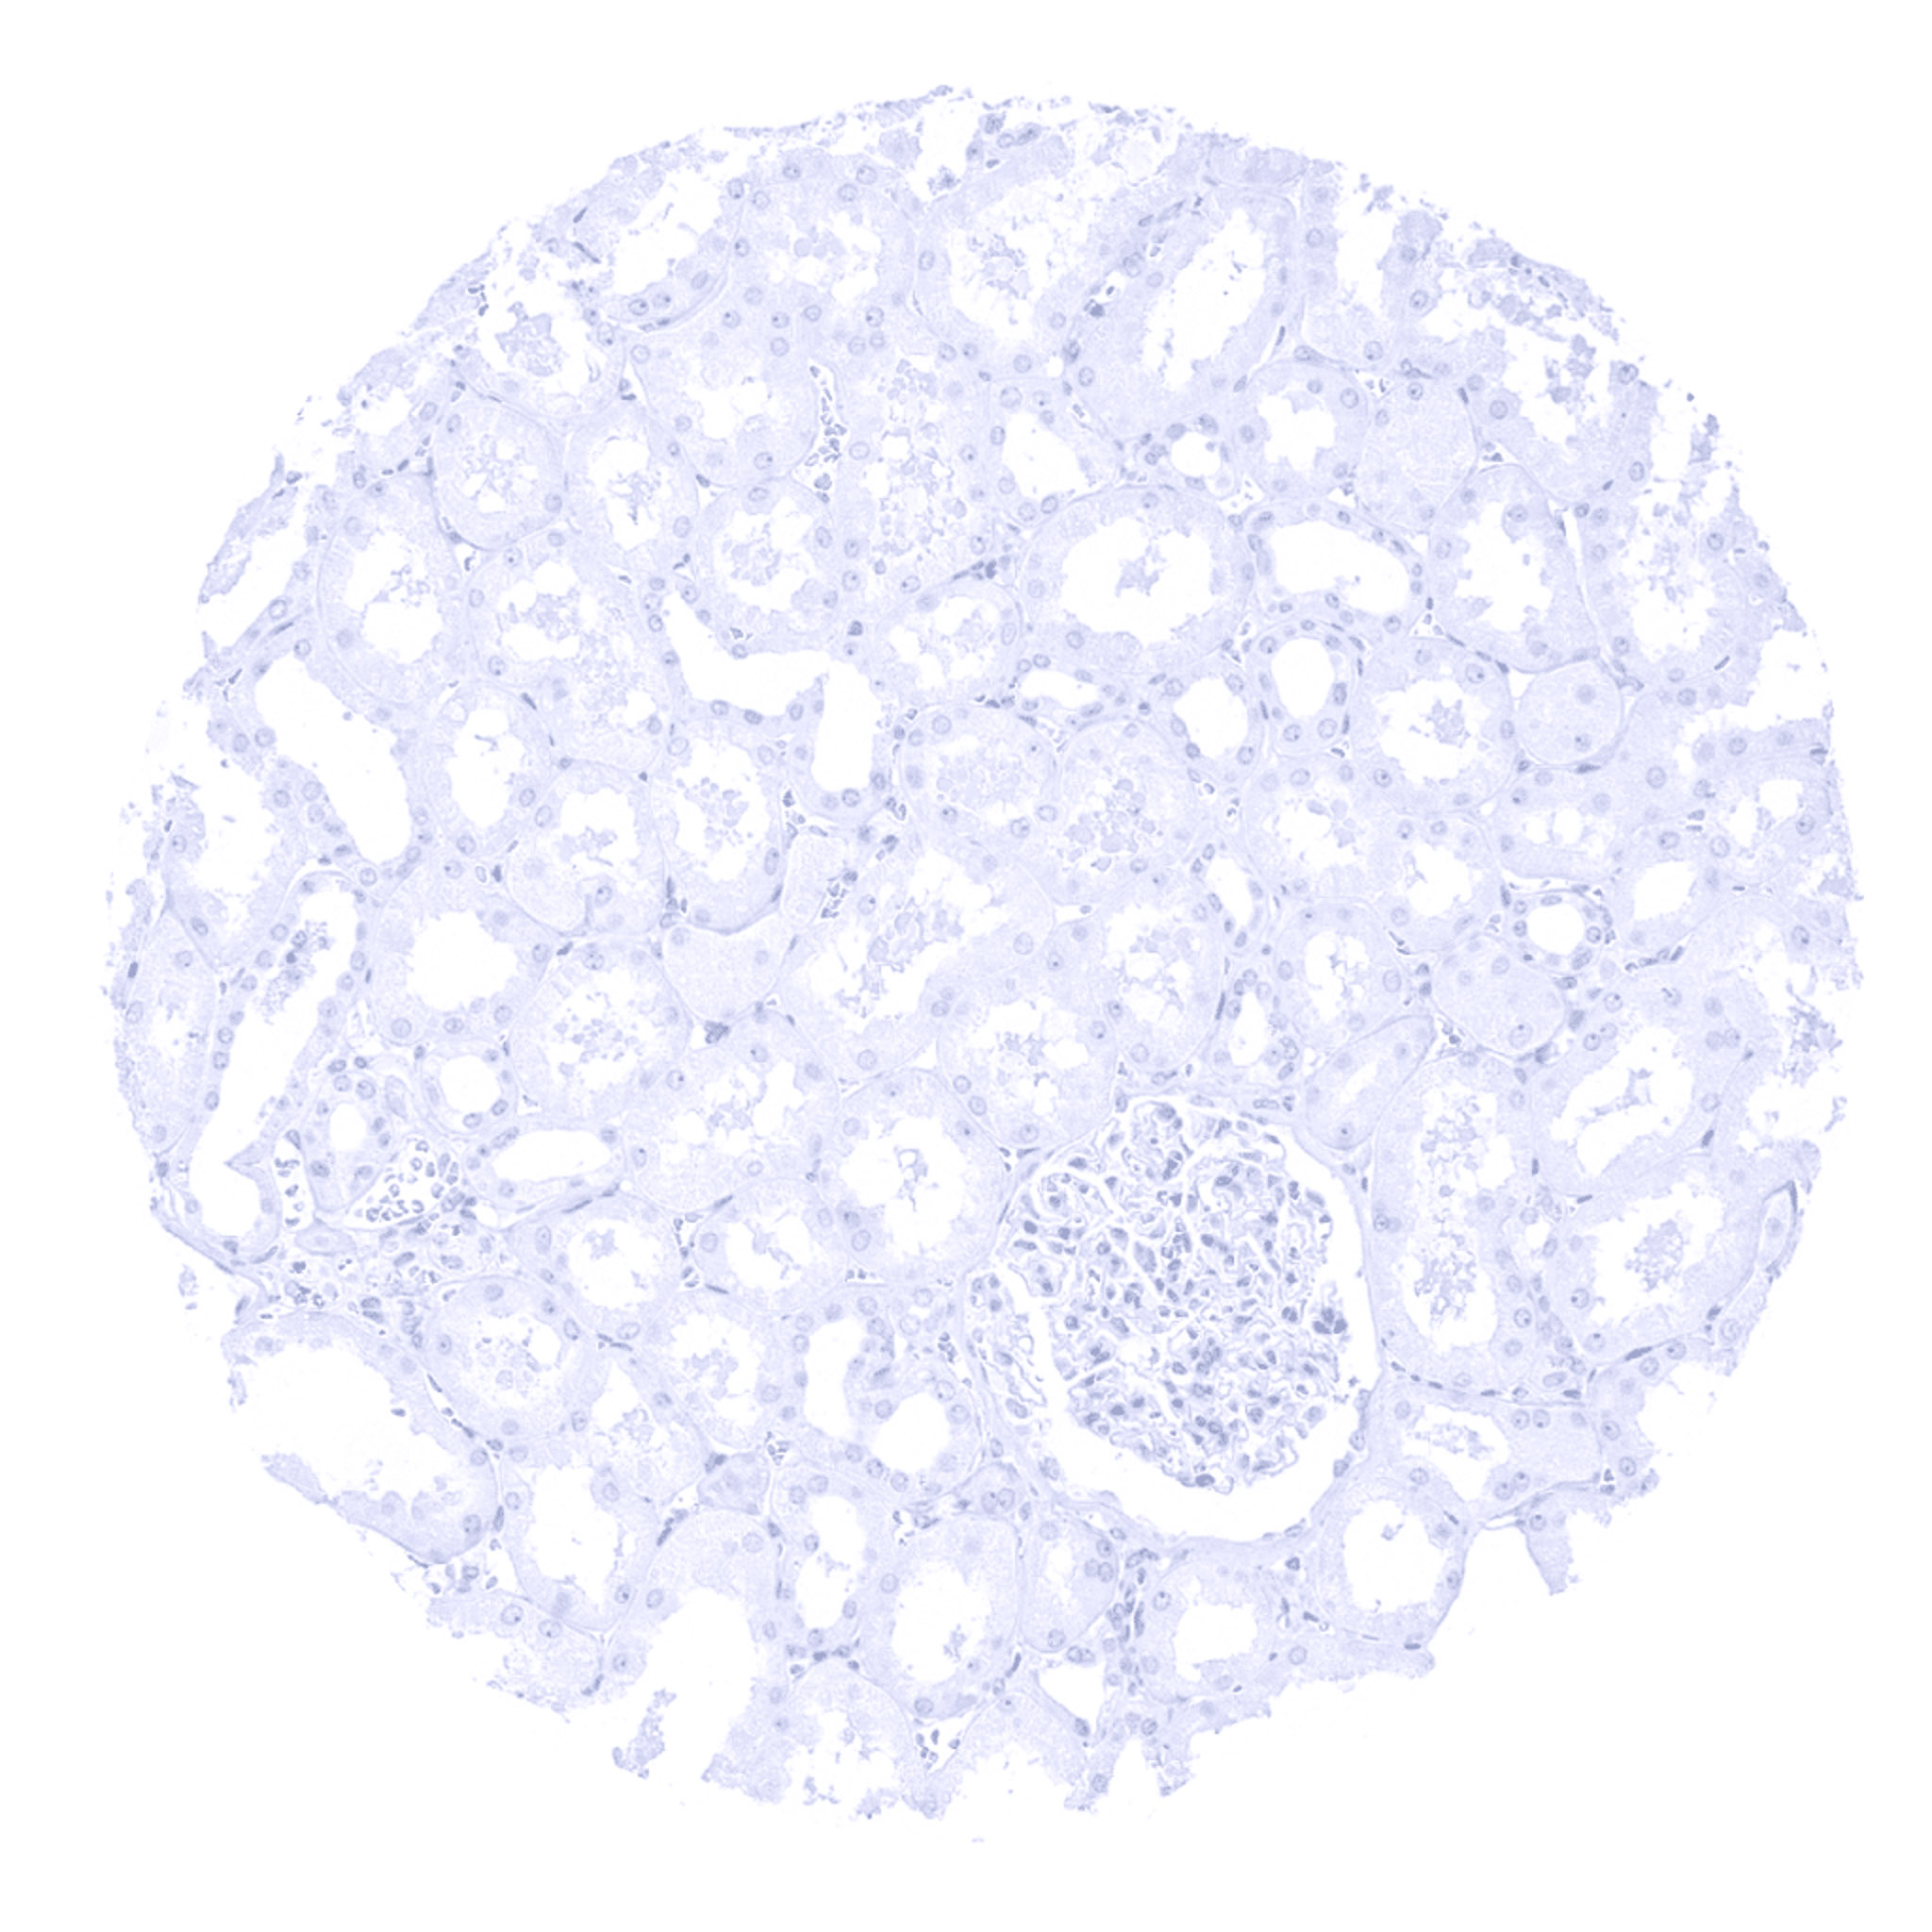

Kidney, cortex